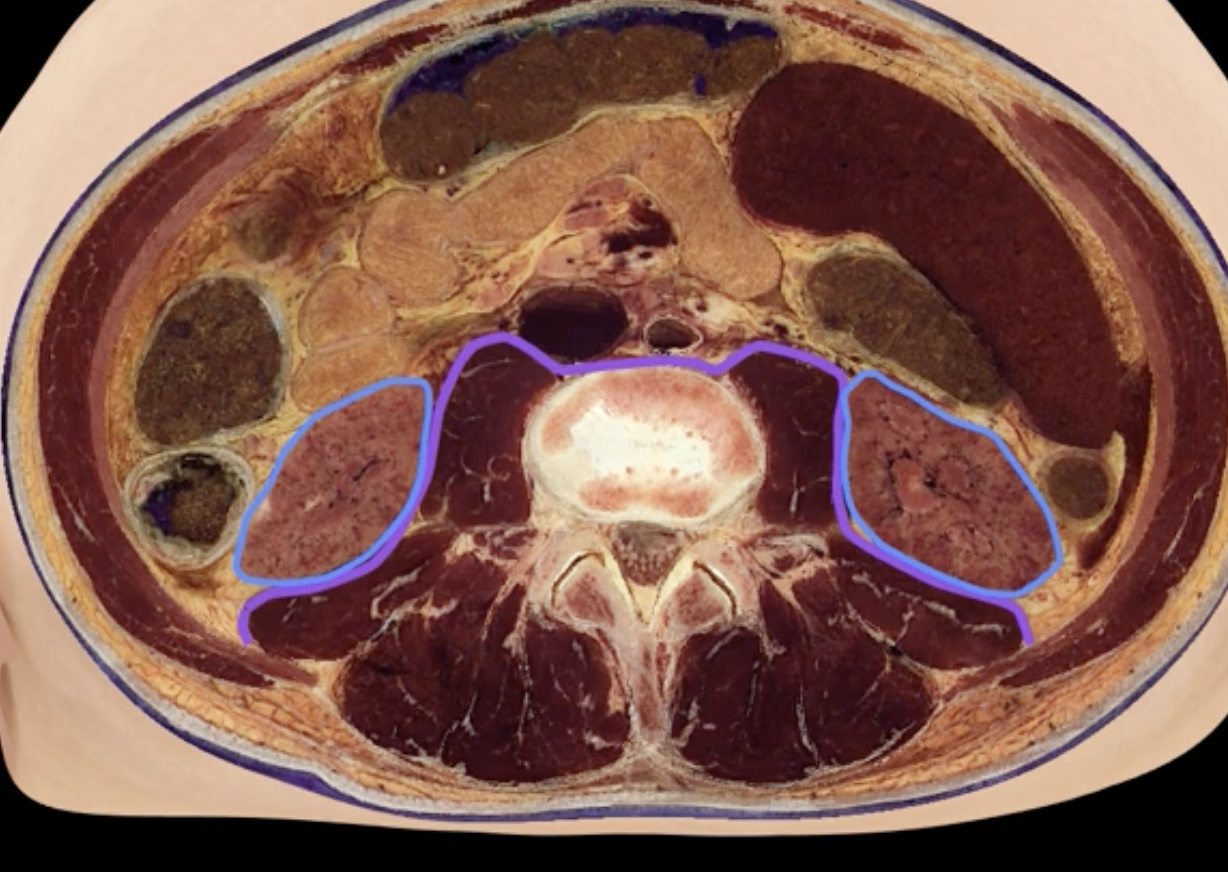

purple

blue: left kidney

yellow: T12

orange: L3

blue, yellow,orange